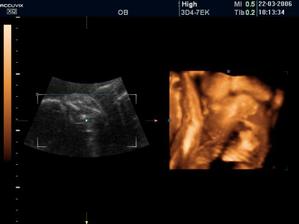

Náš pokladík Viktorko sa narodil 28.7.2006 o 19:20. Vážil 3650 g a meral 52 cm 😉.